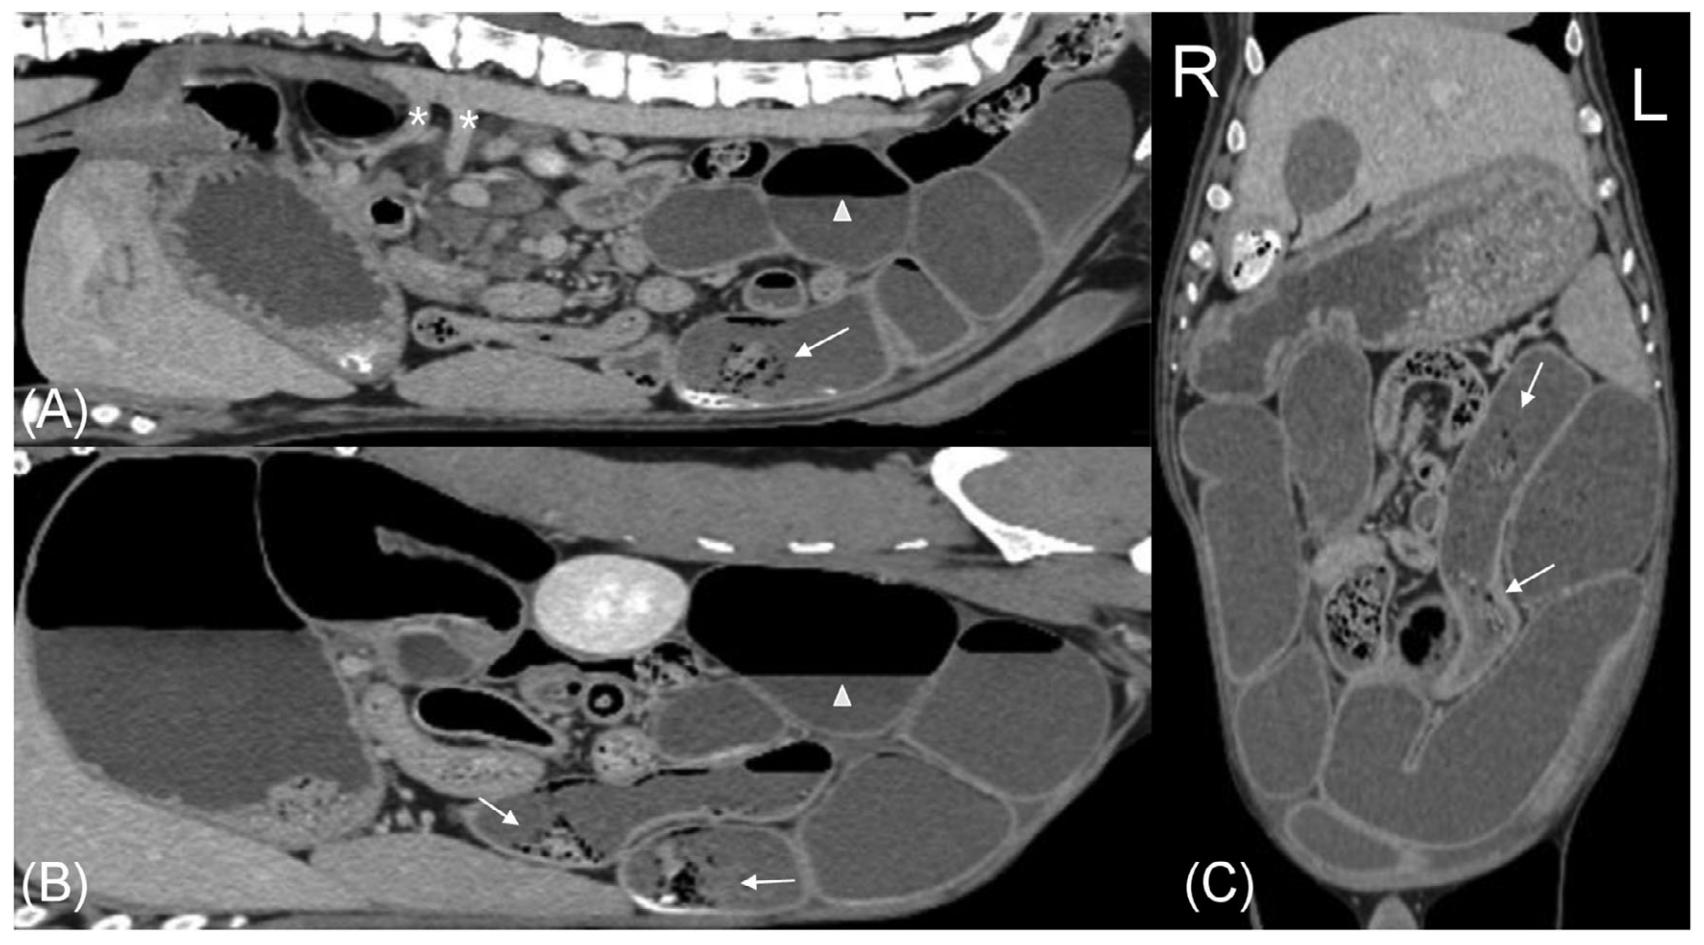

腹部CT显示胃中度扩张,内含气体、不均匀软组织和颗粒状矿物质,小肠严重弥漫性扩张(约为L5高度的4倍),肠腔内充满液体、气体以及不同量的颗粒状矿物质和不均匀软组织。小肠内液体和气体分层,形成水平的气液界面,提示蠕动减少或缺失(下图)。小肠内的颗粒状矿物质和不均匀软组织未占据整个肠腔,未被视为梗阻性病变,因此影像学诊断为弥漫性功能性肠梗阻

胃肠道壁厚度均匀,未见异常肠壁增厚或对比增强改变。CT血管造影的所有阶段均显示正常血管增强,排除了血栓栓塞性疾病或肠系膜扭转/肠扭转作为引起广泛严重肠梗阻的原因。未发现腹膜病变。

↑ 对比后静脉期CT图像,显示正中矢状面(A)、左侧旁矢状面(B)和背平面(C)。在AB中,头部在左侧,在C中,头部在上方。大部分小肠中度弥漫性扩张,内含均匀软组织和气体的混合物,形成依赖重力的气液界面(白三角)。几个小肠段内有少量不均匀的软组织、矿物质和气体衰减物质,但未完全充满肠腔(白箭头)。在A中,腹腔动脉和肠系膜上动脉有正常的对比剂充盈(*)。

↑ 横断面对比后静脉期CT图像,所有图像中均可见中度胃和小肠扩张。X光检查中发现的胃内颗粒状矿物质仍然存在(黑箭头)。大部分小肠段内均匀软组织和气体的分层,形成依赖重力的气液界面(白三角)。几个小肠段内有少量颗粒状矿物质和不均匀软组织,但未完全充满肠腔(白箭头)。胃和小肠的肠壁厚度及对比增强均正常。